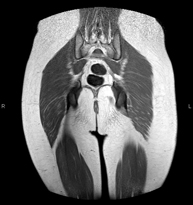

- RM de Sacroilíaques

Prova diagnòstica no invasiva que consisteix en l'obtenció d'imatges d'alta definició anatòmica de les articulacions sacroilíaques mitjançant l'ús d'un camp electromagnètic i ones de ràdio (amb un emissor i un receptor). No utilitza radiació ionitzant. Indicacions: dolor sacroilíac inflamatori. - RM ATM (Articulació temporo-mandibular)

Exploració per a l'estudi de lesions a tendons, músculs i articulacions coxofemorals. Permet identificar de manera precoç l'artrosi de maluc. Resulta molt útil per detectar les bursitis i l'osteopatia dinàmica de pubis, freqüent en esportistes. La durada aproximada és de 20 minuts. No utilitza radiació ionitzant. - RM de Sacroilíaques

Estudi específicament dissenyat per valorar aquestes articulacions i la seva inflamació en els pacients que pateixen espondilitis anquilosant. També resulta d'utilitat en pacients amb traumatismes i possibles fractures del sacre i el còccix. La durada aproximada és de 16 minuts. No utilitza radiació ionitzant. - RM de Glutis